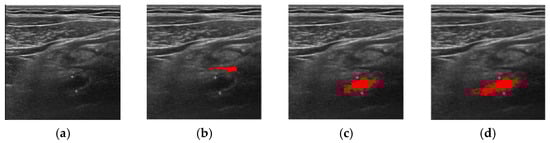

| Method | Successful Images/Total Images |

|---|---|

| FCM | 83/100 |

| ORFCM | 88/100 |

| DFCM | 91/100 |

| DORFCM | 98/100 |

| Accuracy | Precision | Recall | |

|---|---|---|---|

| DORFCM | 84.20% | 83.40% | 85.80% |

| DFCM | 80.80% | 80.90% | 80.20% |

| DORFCM | 84.82% | 83.78% | 86.04% |

| ORFCM | 81.23% | 78.56% | 80.53% |